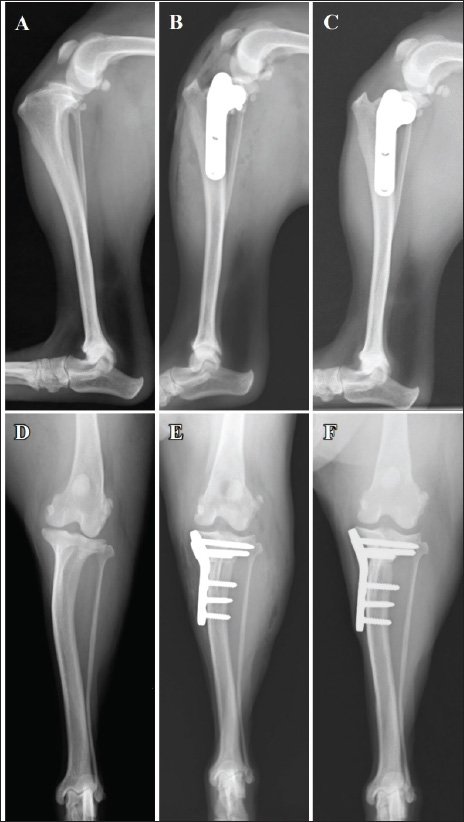

Fig. 1. Mediolateral radiographs (A–C) and caudocranial radiographs (D–F) of the right limb. The infrapatellar fat pad sign and cranial tibial luxation at the first visit (A). Absence of angular limb deformities (D). Placement of a 2.4-mm TPLO plate (B and E). No osteotomy line at the 14-week follow-up (C). No evidence of dislocation at the 14-week post-TPLO (F) follow-up.

Fig. 3. LFTS following the TPLO plate placement in the right hind limbs. The nylon suture is passed around the lateral femoral fabella. Both ends of the suture are passed under the patella ligament subsequently. One end of the suture is passed proximally, and the other end of the suture is passed distally to the cranial screw (asterisk) under the TPLO plate (A and B). The surgeon’s knot is ligated on the caudal side of the TPLO plate (arrow, B). Left weight-bearing lameness with pain upon hyperextension and swelling in the left stifle joint were reported 8 weeks post-surgery of the right limb. The results of the cranial drawer and tibial compression tests performed as a part of the orthopedic examination of the left limb were positive. Radiography revealed the presence of the infrapatellar fat pad sign and cranial tibial luxation at the left stifle joint, with no obvious angular limb deformities (Fig. 4A and D). Ultrasonography of the left stifle joint revealed complete CCLR, moderate joint effusion, and medial buttress without damage to the caudal horn of the medial meniscus (Fig. 5A–C). Preoperative radiographs revealed a TPA of 25°. A 2.4-mm TPLO plate (VP4404-L3; DePuy Synthes Japan, Japan) was selected for TPLO. Identical to the measurements for the right limb, D1 and D2 for the left limb were 7.5 and 8.2 mm, respectively. Arthroscopy and surgery were performed under general anesthesia. Arthroscopy revealed complete CCLR and medium-stage angiogenesis of the caudal cruciate ligament with no damage to the medial meniscus observed (Fig. 6A). A No. 11 blade was used to remove the remaining portion of the cranial cruciate ligament. TPLO of the left limb was performed as described previously. LFTS was placed in the same manner as described previously owing to tibial cranial subluxation and internal rotation intraoperatively post-TPLO (Fig. 6B and C). Subluxation or rotation was not observed following the second tibial compression test. The medications administered post-surgery of the right limb were also prescribed based on postoperative radiographs (Fig. 4B and E). Postoperative radiography revealed that the TPA was 5° on both sides. The owner was satisfied with the postoperative weight-bearing ability of the limb while walking at the 4-week follow-up visit. A faint osteotomy line was visible, and radiography revealed aligned and positioned TPLO plates and bone segments with no displacement. No tibial translocation was detected during the compression test. The dog was able to use its right hind limb without any discomfort at the 8-week follow-up visit. The osteotomy line had disappeared, and radiography revealed aligned TPLO implants. Tibial translocation was not detected during the compression test. Minimal discomfort upon waking up was reported at the 14-week follow-up visit for the right limb (4-week follow-up for the left limb); lameness was not observed while walking or trotting. The tibial compression test results were negative for both limbs, and the rotated bone fragment showed complete fusion with the tibia of the right limb (Fig. 1C and F). A faint osteotomy line was observed in the tibia of the left limb. Radiography revealed no dislocation of the bone or the TPLO implants on the right or left sides. The owner was pleased with the significant improvement in walking ability. By the 13-week follow-up visit osteotomy line in the left limb was not visible, with no residual discomfort or lameness in either limb. The osteotomy line was not apparent owing to bone union (Fig. 4C). The implant alignment and bones remained stable (Fig. 4F). DiscussionBoth limbs exhibited tibial instability post-TPLO in this patient. Although no injury of medial meniscus in the right limb was identified on gross inspection, arthroscopy in the left limb was performed to clarify the cause of the pivot shift phenomenon post-TPLO in the right limb. The pivot shift phenomenon was observed in the left limb following TPLO despite arthroscopy revealing no damage to the meniscus. Further, the TPA of both limbs was identical before and after TPLO. The pivot-shift phenomenon, characterized by uncontrolled internal rotation of the tibia while bearing weight post-TPLO, was noted (Knight and Danielski, 2018). The specific cause of this phenomenon remains unknown; however, it may be attributed to medial meniscectomy, angular deformity, tibial torsion, or excessive internal rotation of the tibia, either independently or in combination (Pozzi et al., 2006; Thieman et al., 2006; Boudrieau, 2009; Knight and Danielski, 2018). Although meniscectomy has been reported to influence the pivot shift phenomenon regardless of changes in TPA post-TPLO, it was not performed in this case (Kim et al., 2012). Restoration of stifle joint stability which retains lameness after TPLO-related pivot shift typically occurs within approximately 4–6 months or may necessitate additional surgery (Wheeler et al., 2003; Gatineau et al., 2011; Bureau, 2017; Knight et al., 2017). Although these findings are specific to large-breed dogs, the pivot shift phenomenon can also occur in toy-breed dogs without meniscal damage in this study. LFTS was applied to both limbs to mitigate internal tibial rotation, as the pivot-shift phenomenon was observed following TPLO plate placement. In addition, lameness or tibial subluxation was not observed for 5 months postoperatively in the right limb. This finding indicates that a combination of TPLO and LFTS may improve stifle joint stability in toy-breed dogs exhibiting intraoperative pivot shift without identifiable cause. The optimal combination of LFTS attachment sites and stifle angles for suture placement varies among dogs (Witte, 2015). To preserve the tension of the LFTS suture and maintain the stifle joint stability, the surgeon’s knot was placed between the caudal side of the TPLO plate and the tibial bones after looping the strand around the cranial screw. Alternatively, passing the strand above and below the plate and ligating the knot on the surface of the plate may also help prevent the pivot shift phenomenon. Nevertheless, we placed the knot on the side of the plate to minimize irritation to the skin covering the plate, as toy-breed dogs generally have thinner skin over the tibial bone compared to large breed dogs. Meanwhile, placing the surgeon’s knot under the plate increases the gap between the tibial bone and the plate, and may exacerbate the instability of the fixation.

Fig. 4. Mediolateral radiographs (A–C) and caudocranial radiographs (D–F) of the left limb. The infrapatellar fat pad sign and cranial tibial luxation at the left stifle joint before the surgery (A). No obvious angular limb deformity can be visualized (D). A postoperative radiograph acquired after the 2.4-mm TPLO plate placement (B and E). The tibial bone and bone fragment are completely fused at 13 weeks post-surgery (C). Additionally, the caudocranial radiograph at the 13-week (F). Follow-up visit shows no sign of dislocation of the implants.